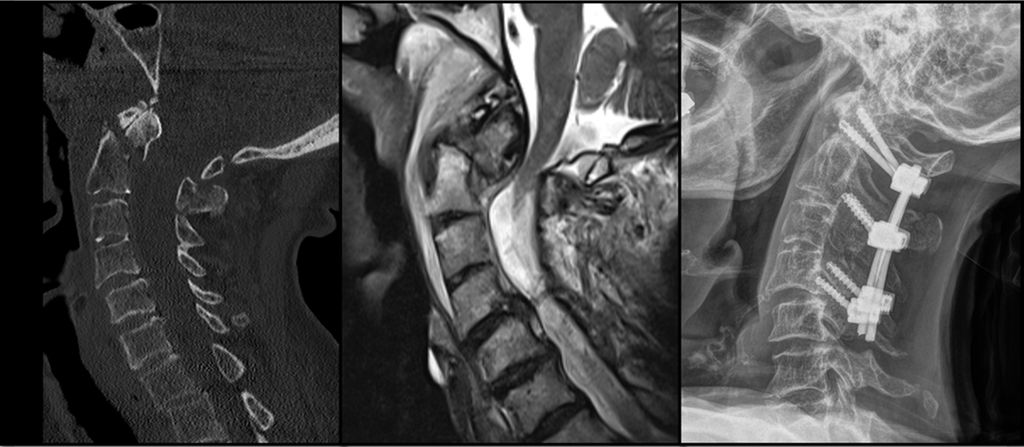

Abb. 2: CT, MRT und Versorgungsstrategie bei einer stark dislozierten Densfraktur Typ IIb mit begleitender Atlasbogenfraktur bei einer geriatrischen Patientin

Etwa 20% aller Wirbelkörperfrakturen im zervikalen Bereich sind Densfrakturen, die typischerweise eine bimodale Altersverteilung aufweisen: Ein kleiner Teil betrifft jüngere, sportlich aktive Männer – die Mehrheit der Betroffenen sind jedoch Frauen über 65 Jahre, welche auf Bodenniveau stürzen.10 Die Mortalität dieser Verletzungen kann mit jener von Schenkelhalsfrakturen im geriatrischen Kollektiv verglichen werden und beträgt rund 14% nach 30 Tagen sowie 44% nach zwei Jahren.11 Eine bestehende Arthrose des atlantoaxialen Gelenks, degenerative subchondrale zystische Veränderungen des Dens sowie eine verminderte Beweglichkeit der subaxialen Wirbelsäule bei geriatrischen Patient:innen erhöhen die mechanische Belastung auf die oberen Segmente der Halswirbelsäule.12 Dies begünstigt an der biomechanischen Schwachstelle – der Densbasis – das Auftreten einer Fraktur.10 Die Klassifikation nach Anderson und D’Alonzo, modifiziert durch Grauer, hat sich aufgrund ihrer prognostischen und therapeutischen Relevanz als Standard für die Einteilung der Densfrakturen etabliert.13,14 Typ I ist eine Abrissfraktur der Ligamenta alaria an der Densspitze, gilt als stabil und wird in der Regel konservativ behandelt. Typ II betrifft den Übergangsbereich des Dens zum Corpus und ist mit Abstand die häufigste Densfraktur, welche als potenziell instabil gilt. Grauer unterscheidet innerhalb der Typ-II-Frakturen die Subtypen IIa (transversaler Frakturverlauf), IIb (Frakturverlauf von anterosuperior nach posteroinferior) und IIc (von anteroinferior nach posterosuperior). Typ III sind Frakturen des Corpus der Axis, welche in der Regel konservativ behandelt werden können. Die Behandlung der Typ-II-Densfraktur bei älteren Patient:innen wird nach wie vor kontrovers diskutiert. Während einige Studien eine operative Versorgung zur Verbesserung der Fusionsrate sowie der Lebensqualität empfehlen, weisen andere darauf hin, dass auch eine konservative Therapie bei geriatrischen Patient:innen ein zufriedenstellendes funktionelles Ergebnis und eine geringe Komplikationsrate ermöglichen kann.11 Die Operationsindikation ergibt sich bei nachgewiesener Instabilität oder bei neurologischer Verschlechterung, etwa infolge einer Myelopathie. Zu berücksichtigen ist, dass bei konservativer Behandlung das Risiko einer Pseudarthrose mit daraus resultierenden chronischen Beschwerden sowie einer möglichen progredienten neurologischen Verschlechterung besonders bei aktiven älteren Patient:innen erhöht ist. Die Blutversorgung des Dens erfolgt überwiegend durch ein Gefäßnetz aus aufsteigenden Ästen der A. vertebralis, das an der Spitze des Dens eine Anastomose und an der Basis einen Gefäßplexus bildet. Diese Gefäßversorgung wird bei Typ-II-Frakturen häufig unterbrochen, was die Knochenheilung negativ beeinflusst.15 Für die Beurteilung der Instabilität gelten folgende Kriterien: eine Dislokation von mehr als 5mm, ein Frakturspalt von über 2mm oder ein kyphotischer Winkel von mehr als 11°.10 Frische IIa- und IIb-Densfrakturen eignen sich für eine ventrale Schraubenosteosynthese. Die dorsale Fusion wird hingegen für IIc-Frakturen, Trümmerbrüche des Dens, stark dislozierte Frakturen sowie bei bereits bestehender Pseudoarthrose bevorzugt.15 Der Halo-Fixateur wird bei geriatrischen Patient:innen heute nicht mehr empfohlen,5,10,11,15 da die Komplikationsrate mit über 30% sehr hoch ist. Häufige Komplikationen umfassen Aspirationspneumonien, Infektionen der Pin-Stellen sowie Druckstellen, Schluckbeschwerden und eine insgesamt erhöhte Mortalität.